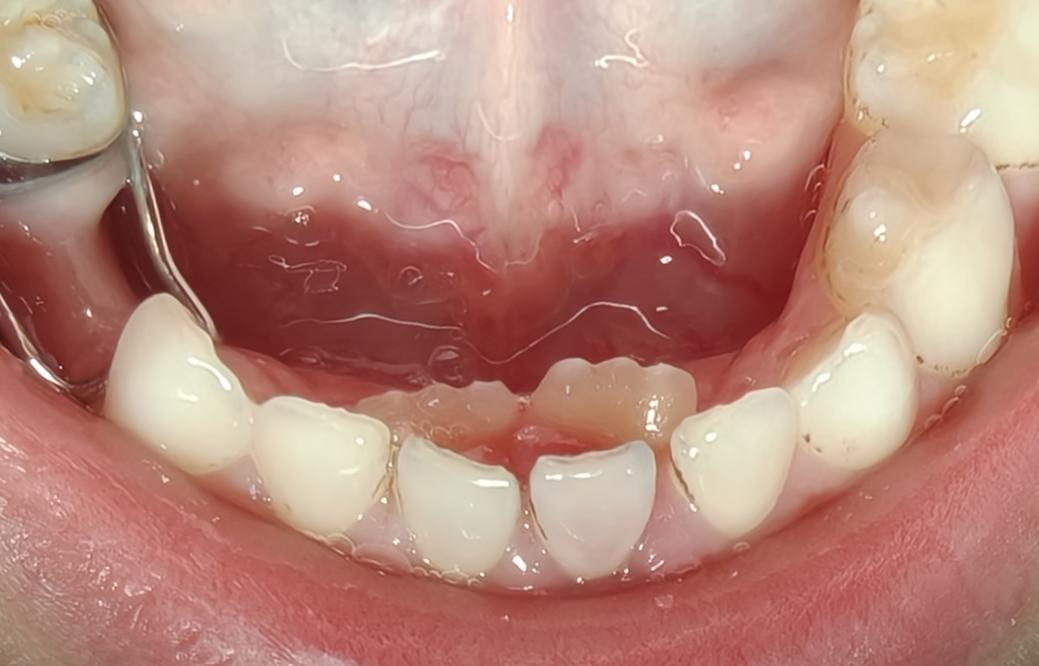

当孩子张开嘴,露出那排典型的双排牙,很多家长都会又惊又笑。这可不是什么超能力,而是儿童口腔科门诊中,我们最常遇到的情况之一——乳牙滞留。

1.最直观的信号:“双排牙”。这是最常见的表现,尤其是在下前牙区。您会看到里面长出了一颗新牙,而外面的乳牙却未脱落,形成内外两排牙齿,像小鲨鱼一样。即使乳牙最终脱落,也可能因为空间被占据,导致新萌出的恒牙排列拥挤、错位。